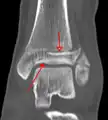

Fracture of both sides of the ankle with dislocation as seen on anteroposterior X-ray. (1) fibula, (2) tibia, (arrow) medial malleolus, (arrowhead) lateral malleolus